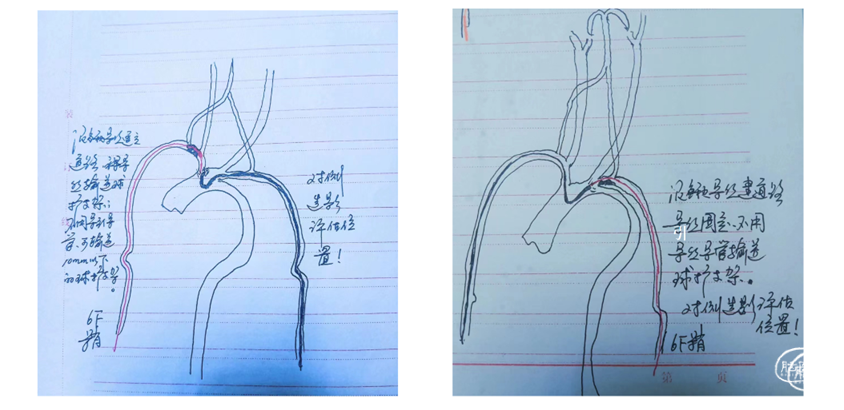

1、通路建立

将猪尾造影导管送入主动脉弓,将260cm泥鳅导丝送入到降主动脉,撤出造影导管,沿导丝送入西蒙导管+6F导引导管组合,尝试将西蒙导管送入到降主动脉成绊未能成功,遂将头端较软的导引导管先送入到降主动脉,再送入西蒙导管,后撤导引导管,西蒙导管成绊,再选入左侧颈动脉,跟进导引导管,回撤西蒙导管,这时导引导管不稳,有下滑的趋势,遂先继续送入导引导管,再回撤西蒙导管,通路建立成功。

2、沿导引导管送入保护装置,释放后,尚导丝送入4-30mm球囊,予以6atm压力扩张,撤出球囊,造影示狭窄。

3、最关键的时刻来了,撤出球囊,沿导引导管送入8-40支架,在支架要过主动脉弓时,导管不稳,有下滑的感觉,远端的保护装置也往下移位,需要进行调整,将保护装置再往上送,缓慢的跟进导管到狭窄处,这样导管的支撑力就够了,再缓慢的送入支架,终于支架安全到位。

支架准确定位后,缓慢的后退导引导管,再缓慢的释放支架,在释放的时候还是有一点张力,释放较困难,需要给点力,支架释放完后,再沿支架输送器往上送导管,造影示有残余狭窄,予以PTA 5-30球囊扩张。

4、球囊扩张后,尚球囊送入导引导管通过支架至C1段远端,将保护装置回收。

本例患者为Ⅲ型主动脉弓,无名动脉与左侧颈总动脉几乎平行、左侧颈总动脉与主动脉弓也是很小的锐角,无论是从上肢入路还是下肢入路都很难建立通路;

本例患者存在经桡动脉入路的诸多障碍,但因患者的强烈需求,最终还是尝试经右侧桡动脉入路进行手术,最终顺利完成,道虽迁,行则将至,面对困难,需要面对,勇于尝试,才能不断进步,但术前也需要做好各种紧急预案,术中小心操作,将风险控制在最小程度。